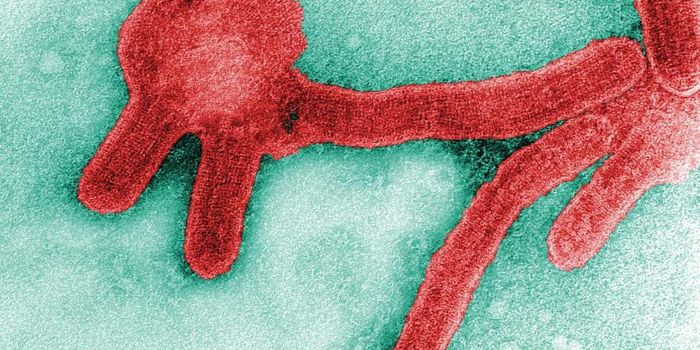

AUG 14, 2018MicrobiologyResearchers have learned how Ebola gains entry to cells, which can help us stop it.

JAN 08, 2019MicrobiologyBats are a vital part of the ecosystem, but they also host deadly viruses. Scientists have now discovered a new filoviru ...

MAY 08, 2022MicrobiologyAfrican fruit bats are the natural hosts of Marburg and Ebola viruses, both of which are filoviruses. These RNA viruses ...